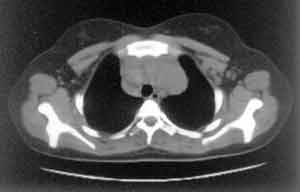

Рис. 1. Передние внутримаммарные лимфоузлы.